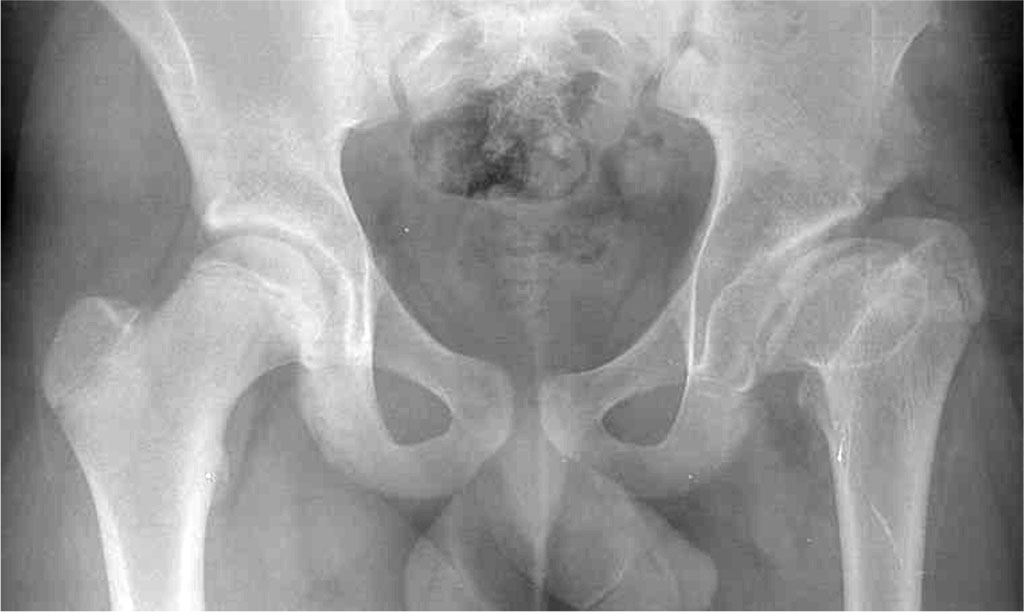

Imaging Diagnostics. The most commonly used imaging method for diagnosing Perthes disease is conventional X-ray imaging performed in two projections: anteroposterior (AP) and lateral. Obtaining images in two planes significantly reduces the risk of diagnostic errors and enables accurate diagnosis. X-ray is considered the gold standard for identifying LCPD. However, it is important to emphasize that conventional X-rays do not provide detailed information needed to assess the structures of the hip joint components. Therefore, magnetic resonance imaging (MRI) is used to evaluate the disease’s progression and to aid in selecting the appropriate treatment method. Another diagnostic tool helpful in LCPD assessment is ultrasonography (USG). The advantages of ultrasound include its wide availability, low cost, and lack of side effects. Additionally, it is a quick and non-invasive examination. This is especially important in young children, for whom diagnostic procedures can be challenging due to limited ability to cooperate and a lack of understanding about the process and purpose of medical examinations. Compared to magnetic resonance imaging, which is time-consuming and requires the patient to remain still, ultrasound usually does not require sedation in young children. Ultrasonography appears to be a good complementary method for evaluating patients with LCPD; however, it should not be used as the sole imaging technique because it is subjective and only visualizes soft tissues. Studies have shown that ultrasound is useful in monitoring joint effusion, assessing femoral head extrusion, and recognizing the healing phase. Computed tomography (CT) has also been applied in LCPD diagnosis, as it depicts areas of osteosclerosis surrounding the necrotic bone and reveals subchondral bone fractures. CT is also used in surgical treatment planning through 3D imaging, allowing detailed three-dimensional visualization of anatomical structures, which enables precise surgical intervention planning and minimizes the risk of complications [2, 26–28]. Another supportive diagnostic method is arthrography — a procedure involving the injection of contrast material into the joint cavity, followed by imaging using one of the aforementioned techniques. This examination allows dynamic assessment of joint compliance in various positions. It is particularly useful in advanced cases with flattening or collapse of the femoral head. In early stages, the arthrographic image may remain normal. Arthrography serves as a valuable tool for assessing disease progression and planning further therapeutic management [33].

The symptoms of Legg-Calvé-Perthes Disease (LCPD) often develop gradually and initially present mildly and non-specifically, which can lead to delays in diagnosis. One of the first and most characteristic symptoms is limping, which may appear suddenly or develop progressively. This is accompanied by restricted hip joint mobility, particularly in abduction and both internal and external rotation. Pain in the hip area is common, often radiating to the thigh or knee, and typically worsens after physical activity. As the disease progresses, a Trendelenburg sign may appear. Some patients also experience morning stiffness of the hip joint. The primary diagnostic method is X-ray imaging in anteroposterior (AP) and lateral projections; however, magnetic resonance imaging (MRI) allows for more accurate evaluation. Although less precise, ultrasound (US) is fast, inexpensive, and safe—making it particularly useful in younger children. Computed tomography (CT) and arthrography serve as supplementary tools, providing detailed anatomical information that aids in surgical planning [24, 33]